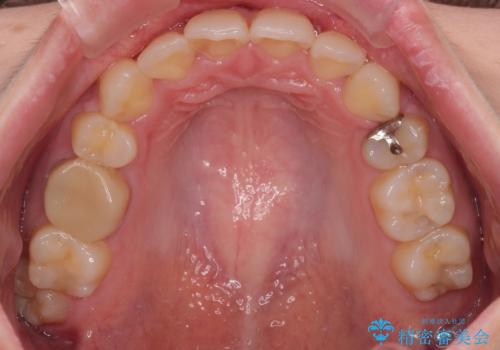

デコボコがスッキリするだけでなく、口元の突出感も少し改善され、満足のいく仕上がりとなりました。

- 八重歯やクロスバイトを気にして来院された患者様です。

口元の突出感はありませんでしたが、デコボコが強く、非抜歯矯正とすると出っ歯仕上がりとなる可能性があったため、上下左右の第一小臼歯4本を抜歯し、ワイヤー装置にて矯正治療を行うこととしました。